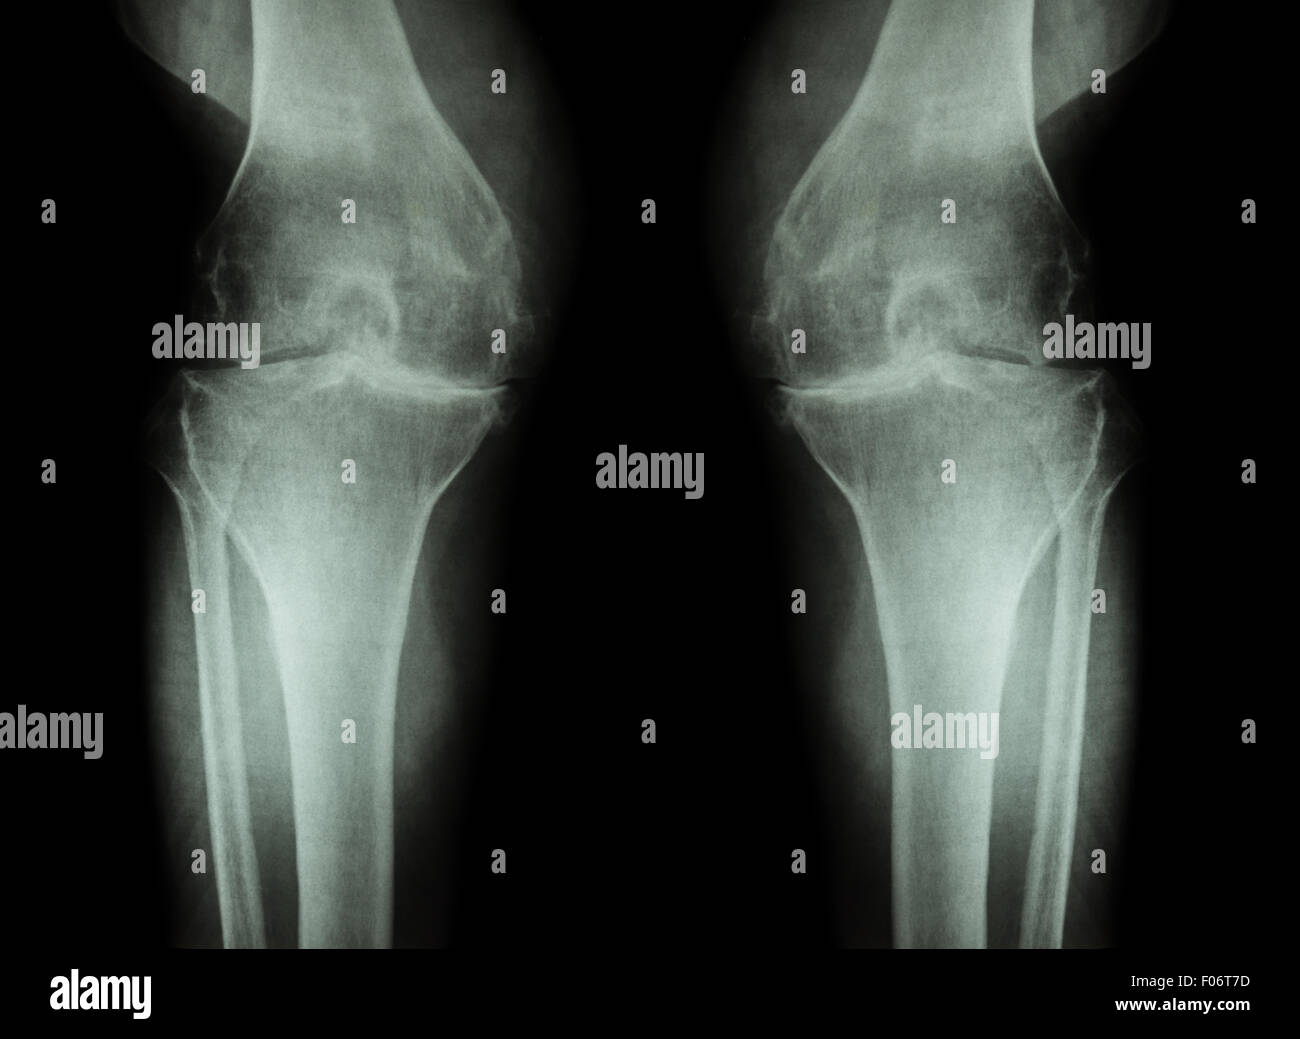

Film Xray Both Knee Joint AP View Name is Rosenberg View for Diagnosis Tunnel View Knee X Ray Tunnel view (intercondylar notch view) demonstrates: The béclere method intercondylar view is an additional projection of the knee, used to better examine the tibial plateau and femoral intercondylar spaces 1. Beam directed at knee joint with 5°cephalad angulation. Horizontal ray (lateromedial) = supine + knee extended. Posterior aspect of femoral condyles, intercondylar notch, intercondylar eminence. Learn about the knee series,. Tunnel View Knee X Ray.